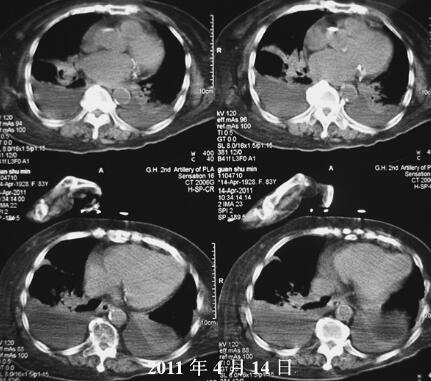

诊治经过:入院时将患者由平车搬至病床时,患者突发严重呼吸困难,大汗,双肺广泛哮鸣音,心电监护示HR 132次/分,BP 148/74mmHg,指氧饱和度(吸氧浓度33%)90%。血气分析(吸氧浓度33%):pH 7.33,PO2 69mmHg,PCO2 46mmHg,HCO3− 23.6mmol/L,BE −1.9mmol/L。考虑突发急性左心衰竭,给予地塞米松10mg静推,毛花苷丙0.4g缓慢静推,特布他林0.25mg缓慢静滴及无创呼吸机辅助通气(模式ST参数:IPAP 16cmH2O,EPAP 6cmH2O,2次/分),约30分钟后呼吸困难缓解,心率降至99次/分。入院后查胸部CT(图3、图4):右侧中下肺片状影,双侧胸腔积液,二尖瓣、主动脉、冠状动脉钙化斑。给予莫西沙星抗感染、多索茶碱+特布他林平喘、氨溴索祛痰、灯盏花素+单硝酸异山梨酯扩张冠状动脉、改善微循环、右侧胸腔闭式引流等治疗。胸腔积液常规:淡黄色,透明,李凡他试验阴性,细胞总数110×106/L,白细胞26×106/L,淋巴细胞74%;ADA 3.10U/L。胸腔积液生化:总蛋白15.1g/L,LDH 96.40U/L,Glu 8.20mmol/L。胸腔积液性质为漏出性,考虑心力衰竭导致。经过治疗,病情明显改善,15日07:05复查血气分析(吸氧浓度33%):pH 7.400,PO2 112mmHg,PCO2 39mmHg, 23.7mmol/L,BE −0.5mmol/L。之后患者喂食时出现呛咳后再次突发喘憋,听诊双肺满布痰鸣音及喘鸣音,立即给予吸痰,吸出大量牛奶及食物残渣,查血气分析(吸氧浓度33%):pH 7.32,PO2 44mmHg,PCO2 59mmHg, 22mmol/L,BE −3.2mmol/L。给予氢化可得松琥珀酸钠200mg静滴,以解痉、平喘、抗过敏,约15分钟后患者症状好转。给予留置胃管,行鼻饲进食。经过加用激素(16、17日氢化可得松琥珀酸钠100mg,18、19日氢化可得松琥珀酸钠50mg)、强心(地高辛0.25mg,每日1次)治疗4日,患者病情逐渐好转,咳嗽、喘憋明显减轻,咳痰减少。但患者之后仍因反复误吸、感染和反复缺氧导致病情逐渐加重,进而心肌损害、心功能不全也进一步加重。继续给予抗感染、强心、碳酸氢钠纠正酸中毒、左侧胸腔闭式引流、间断无创呼吸机辅助通气等进一步治疗3日,病情仍有反复(图5)。患者家属要求放弃气管插管等有创抢救措施,于4月24日14:00患者心率、血压突发下降,经抢救无效,于24日14:37死亡。

图3 入院后胸部X线CT(肿瘤)

图4 入院后胸部CT(纵隔瘤)